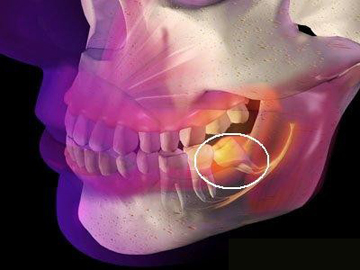

2、手術(shù)復(fù)雜性:拔智齒手術(shù)的復(fù)雜性也會(huì)影響費(fèi)用,如果智齒生長(zhǎng)位置正常,手術(shù)相對(duì)簡(jiǎn)單;如果智齒被埋在骨頭里,需要切開(kāi)牙齦和骨頭,手術(shù)難度增大,費(fèi)用相應(yīng)增加。